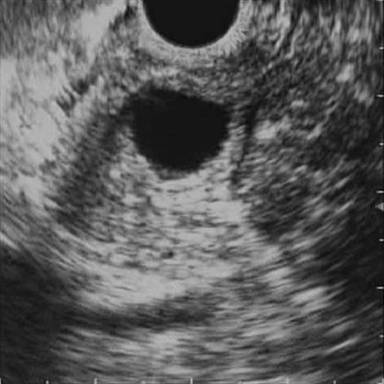

A 63-year-old male had two episodes of acute pancreatitis by biochemistry and abdominal ultrasonography. EUS findings showed an ampullary mass and cystic dilatation of terminal portion of duct of Wirsung suggestive of wirsungocele (Figures 1 and 2). EUS guided FNA from the ampulla suggested a neuroendocrine tumor. MRCP confirmed EUS findings of wirsungocele and ampullary mass (Figure 3). ERCP (Figure 4) and endoscopic ampullectomy was then performed and patient made an uneventful recovery. The histopathological examination and immunohistochemistry showed neuroendocrine tumor (pathological classification: G1) with cells expressing synaptophysin and chromogranin (Figure 5). The Mib proliferation index was less than 2%. The pancreatic duct was seen well dilated within the tumor tissue.

Figure 1. EUS of the ampulla of Vater showing cystic dilation of terminal pancreatic duct. |